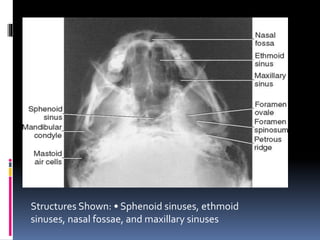

 Sphenoid, posterior Ethmoid and Maxillarry sinuses

(seen best in that order)

Structures Shown: • Sphenoid sinuses, ethmoid

sinuses, nasal fossae, and maxillary sinuses